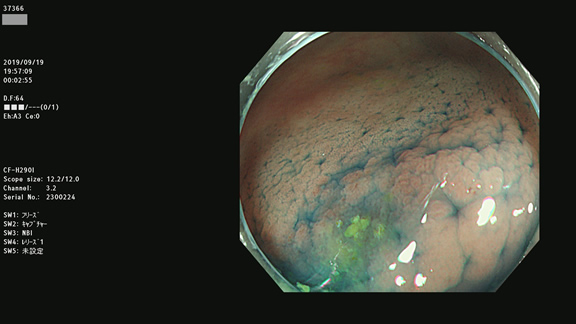

非典型的ポリープの例

炎症性のビランに見えますが・・・腺腫です(病理で確定ずみ)。